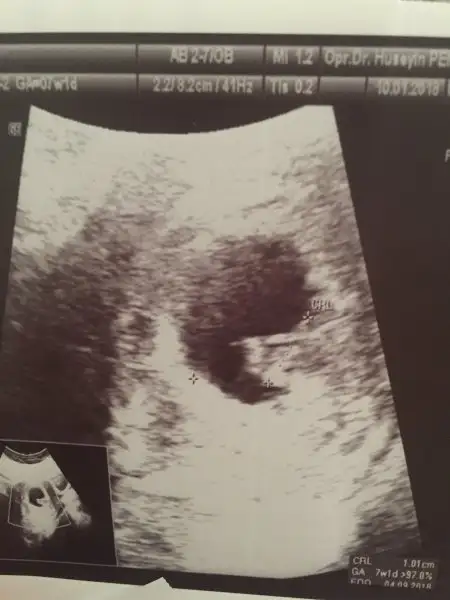

interiorarchitect interiorarchitect canım benim minakka da tahminde bulunabilirmisin :) karından usg kalp atışı 164

Eklentiler

• 39079F02-0DB2-4376-9219-091D3F26CBEC.webp

39079F02-0DB2-4376-9219-091D3F26CBEC.webp

12,5 KB · Görüntüleme: 72